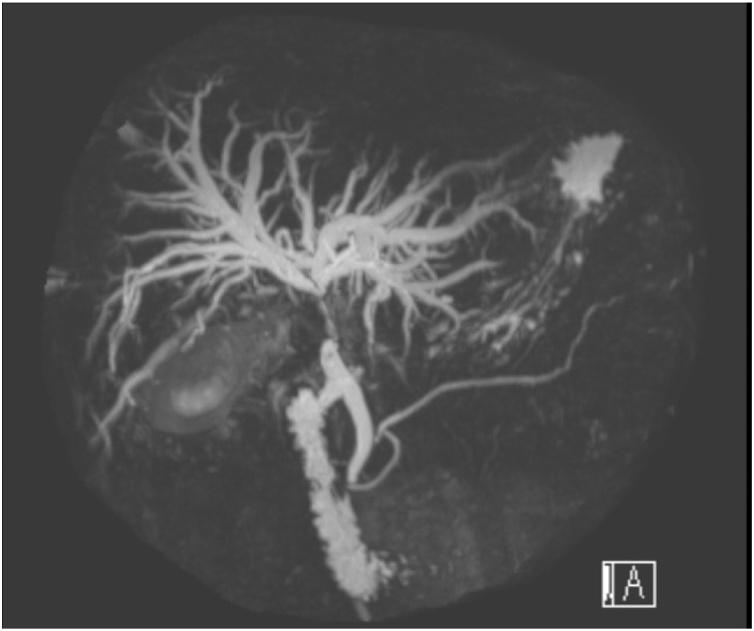

一名48岁男性因胆绞痛和体重减轻前来就诊,超声检查发现有胆结石。在随后的随访中,他出现了深度黄疸,肝功能紊乱,CT显示有胆囊肿块和胆管扩张。后续的磁共振胰胆管造影(MRCP)提示为XGC并伴有MS,但不能排除恶性病变。在为其黄疸进行经皮胆道引流时,术前细针穿刺抽吸细胞学检查(FNAC)显示为XGC,无恶性证据。鉴于腹腔镜检查时炎症严重且积脓张力高,他接受了开窗式胆囊次全切除术。最终的组织病理学诊断为急性胆囊炎。

我们的患者可能最初患有未被识别的急性胆囊炎,进而发展为伴有积脓和I型Mirizzi综合征的复杂肿块,最终导致类似胆囊癌的严重梗阻性黄疸。鉴于在这些严重炎症病例中进行腹腔镜胆囊全切除术很危险,开窗式胆囊次全切除术已被证明是一种比更具侵入性的手术策略更安全的替代方法,并成功应用于我们的患者。